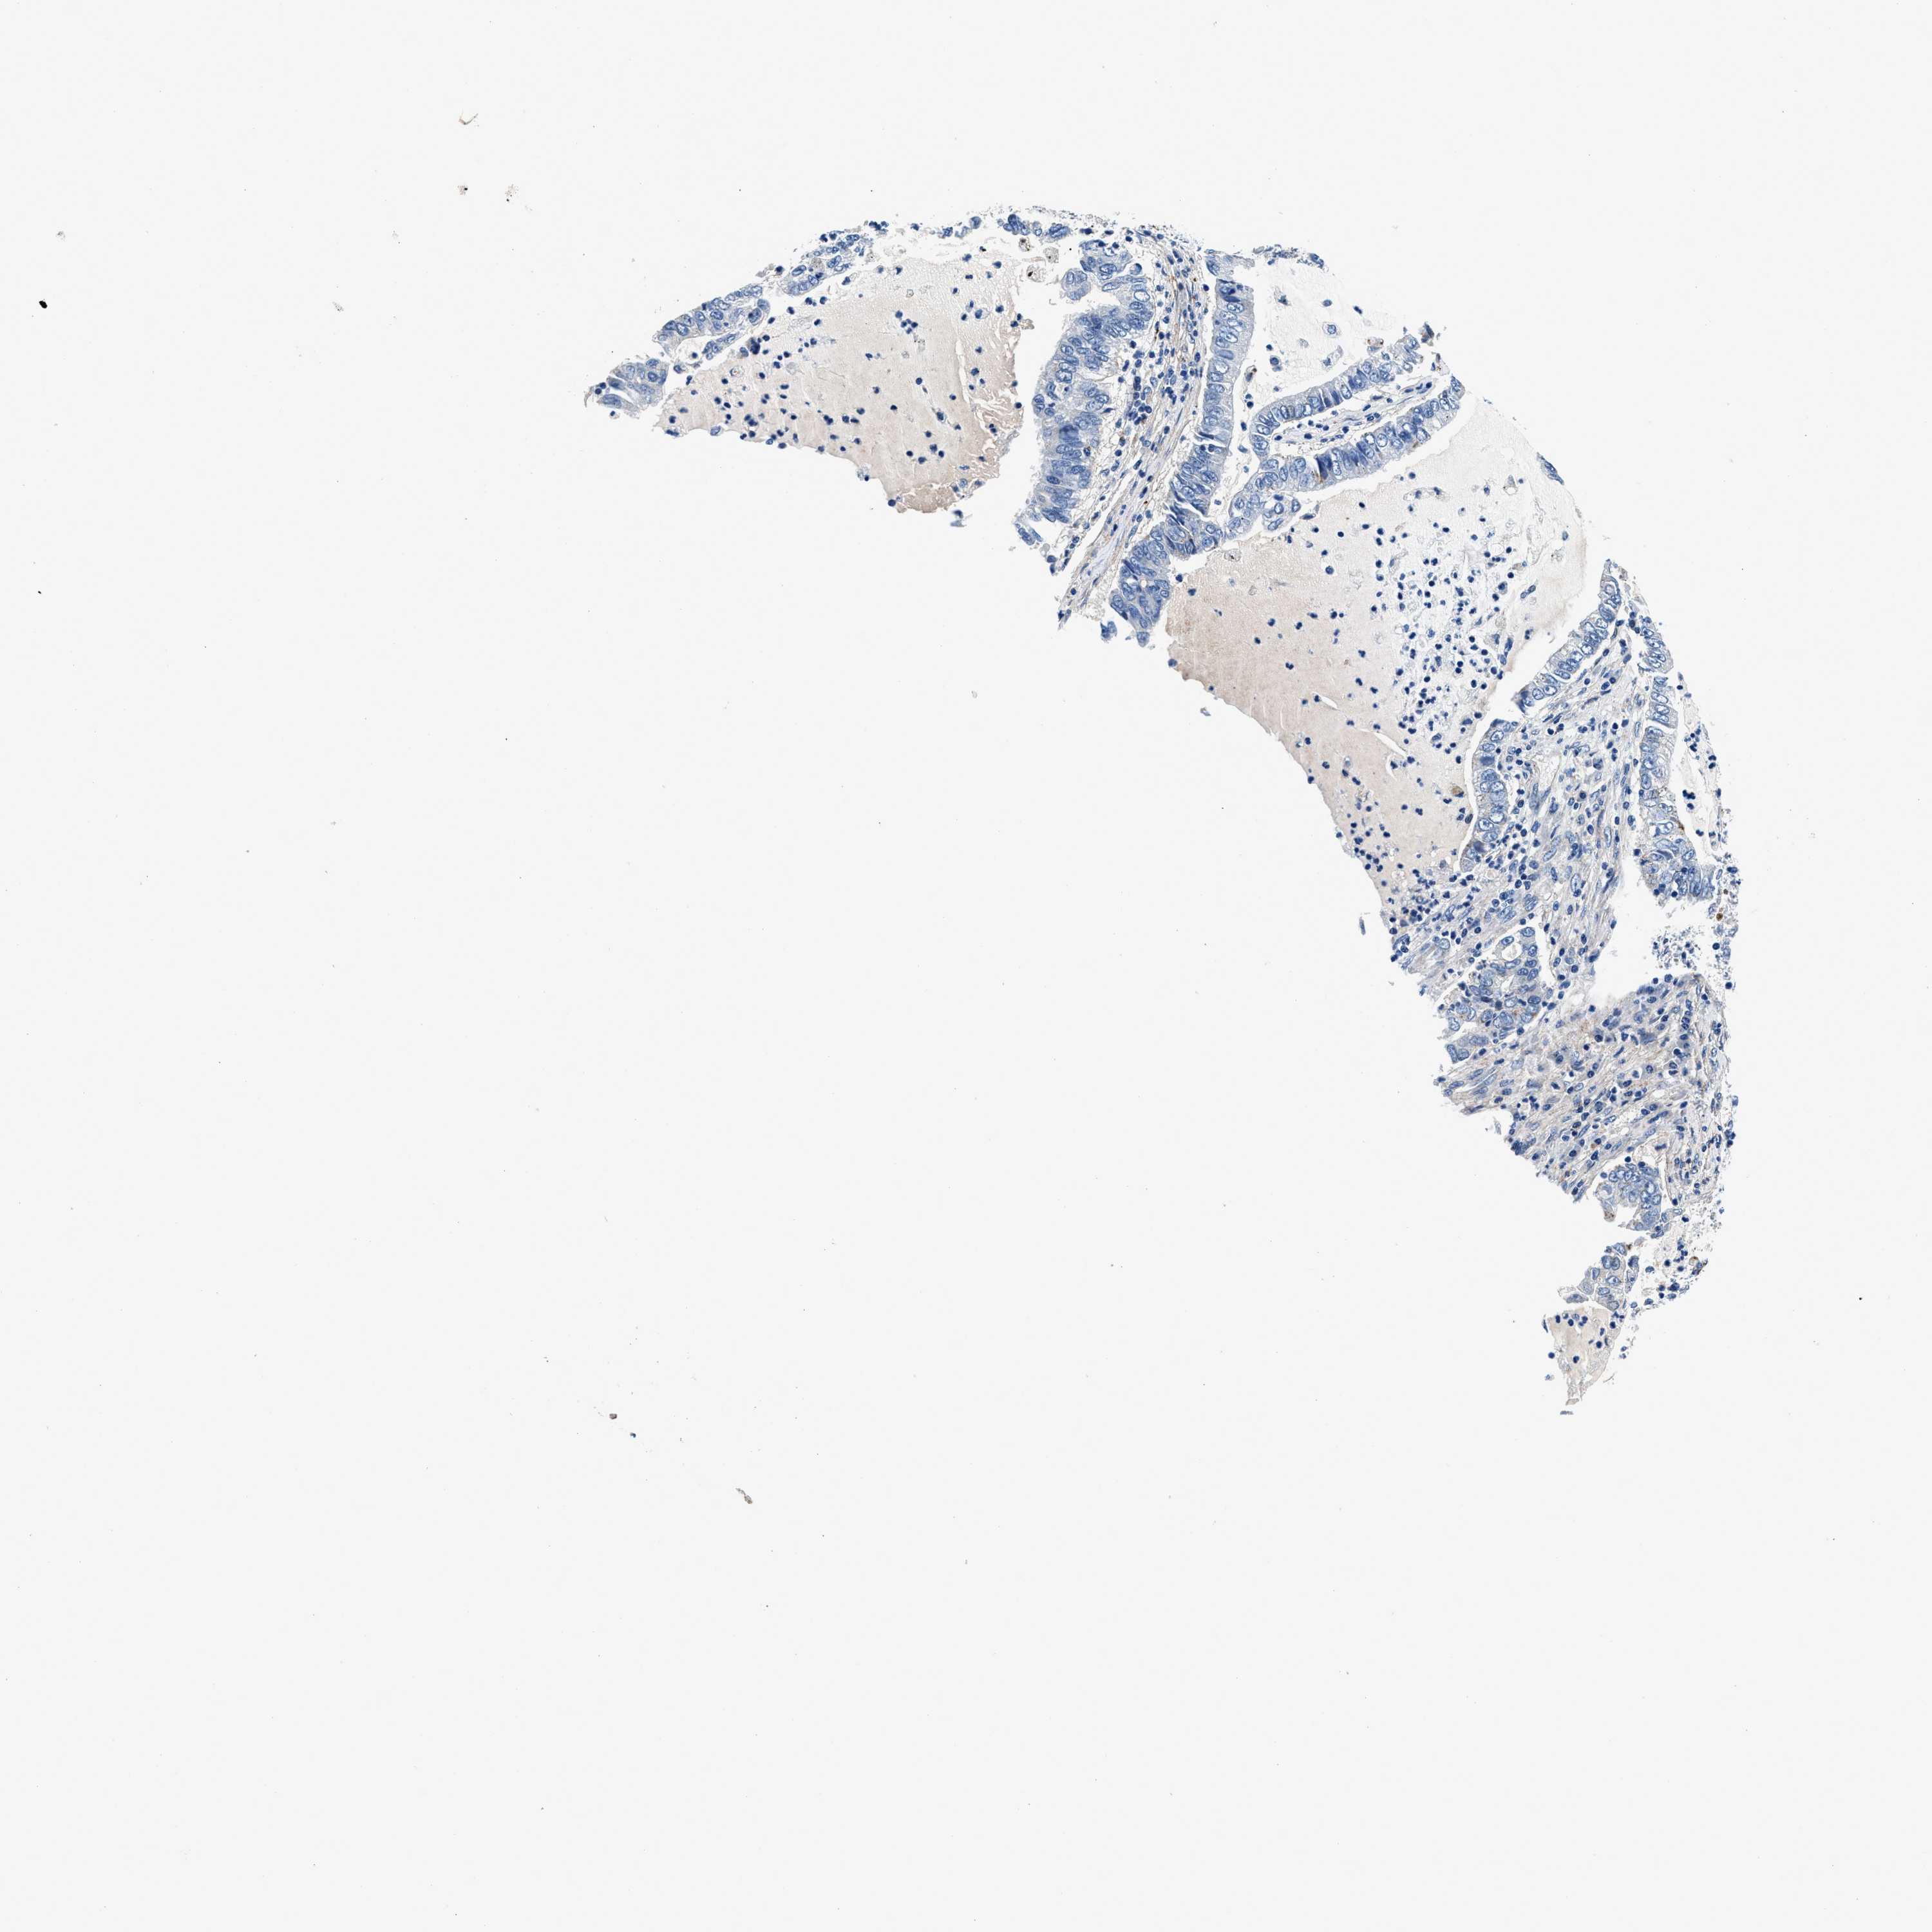

LUNG ADENOCARCINOMA (VALIDATION) - Interactive survival scatter ploti

The Survival Scatter plot shows the clinical status (i.e. dead or alive) for all individuals in the patient cohort, based on the same data that underlies the corresponding Kaplan-Meier plots. Patients that are alive at last time for follow-up are shown in blue and patients who have died during the study are shown in red.

The x-axis shows the expression levels (FPKM) of the investigated gene in the tumor tissue at the time of diagnosis. The y-axis shows the follow-up time after diagnosis (years). Both axes are complimented with kernel density curves demonstrating the data density over the axes. The top density plot shows the expression levels (FPKM) distribution among dead (red) and alive patients (blue). The right density plot shows the data density of the survived years of dead patients with high and low expression levels respectively, stratified using the cutoff indicated by the vertical dashed line through the Survival Scatter plot. This cutoff is automatically defined based on the FPKM cutoff that minimizes the p-score. The cutoff can be changed by dragging the vertical line or by entering a cutoff value in the square labeled "Current cut-off".

Under the Survival Scatter plot the p-score landscape (black curve; left axis) is shown together with dead median separation (red curve; right axis). Dead median separation is the difference in median mRNA expression between patients who have died with high and low expression, respectively. It is calculated as follows: median FPKM expression of dead patients with high expression - median FPKM expression of dead patients with low expression. This is intended to aid the user in visually exploring custom cutoffs and the associated p-scores and dead median separation.

Individual patient data is displayed and can be filtered by clicking on one or more of the category buttons on the top of the page. Categories describing expression level and patient information include: high, low, alive, dead, female, male and tumor stages. The scale of the x-axis can be toggled between linear and log-scale by clicking on the "x log" button. Mouse-over function shows TCGA ID, patient information and mRNA expression (FPKM) for each patient.

& Survival analysisi

Kaplan-Meier plots summarize results from analysis of correlation between mRNA expression level and patient survival. Patients were divided based on level of expression into one of the two groups "low" (under cut off) or "high" (over cut off). X-axis shows time for survival (years) and y-axis shows the probability of survival, where 1.0 corresponds to 100 percent.

DAG1 is not prognostic in Lung Adenocarcinoma (validation)

: 51.45